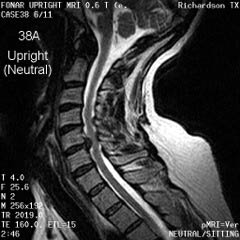

![]() |

Cervical Spine |

|

Upright Neutral |

Upright Extension |

Unsuspected

Disc Herniation in Extension |

Figure 8.

Figure 8a-8d.

Further examples of the exceptional anatomic detail

made visible by the DISCOVERY

of Damadian of the pronounced differences in the decay

rates (relaxations) of the NMR signals

of the body's normal tissues (Figure

6). The DISCOVERED

differences supply the pixel amplitude differences

"PIXEL CONTRAST (IMAGE DETAIL)"

that produce, for the first time in medical history,

the detailed visualization of normal human anatomy

MRI is noted for. Note the visualization of the